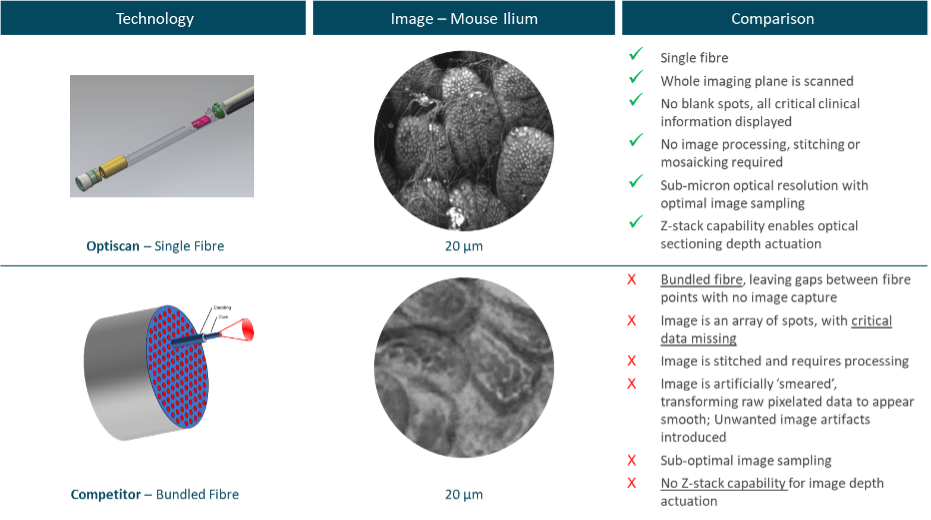

- Laser Scanning: A single optical fiber projects a pinpoint of laser light into the live tissue in a scanned raster pattern.

- High-Resolution Imaging: Up to 1000x real-time magnification, revealing subcellular details (0.55 µm resolution).

- 3D Imaging Capability: Z-axis focus for comprehensive three-dimensional imaging, with depth capabilities up to 400 µm.